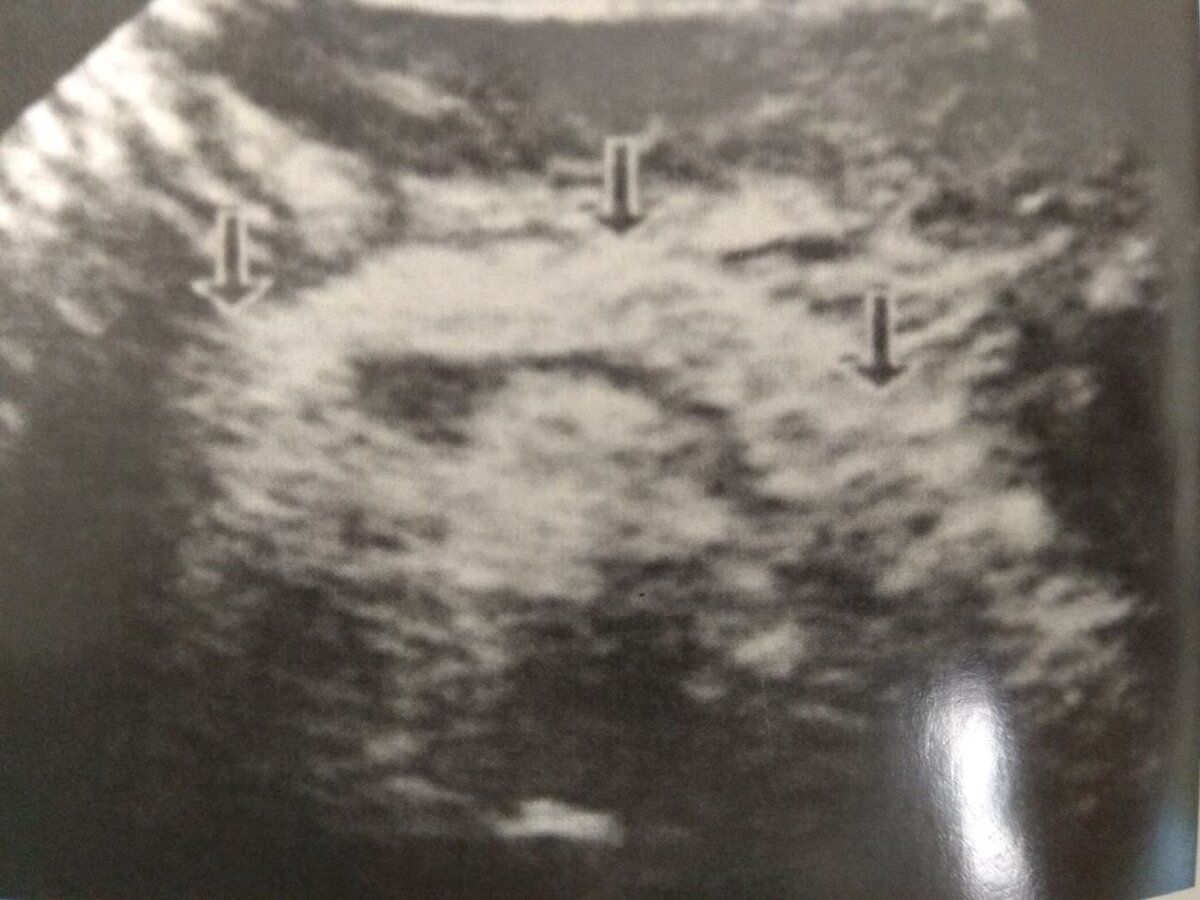

Вот так выглядит хронический панкреатит на УЗИ

Источник: Ультрасонография органов желудочно-кишечного тракта Р.Я Аблуллаев

Ультразвуковая картина хронического панкреатита зависит от активности процесса, однако есть некоторые ключевые характеристики этого патологического процесса:

• В большинстве случаев форма ПЖ сохранена

• Повышается эхогенность ПЖ (железа становится светлее)

• Появляется неоднородность структуры железы: зубастости или бугристости

• Изменяются размеры ПЖ: она может как увеличится в размерах, так и уменьшиться

• Могут визуализироваться участки неправильной формы, которые называются псевдотуморозными. Это результат фиброза и хронического воспаления - требует обязательного дообследования и контроля. Высокий риск перерождения в рак.